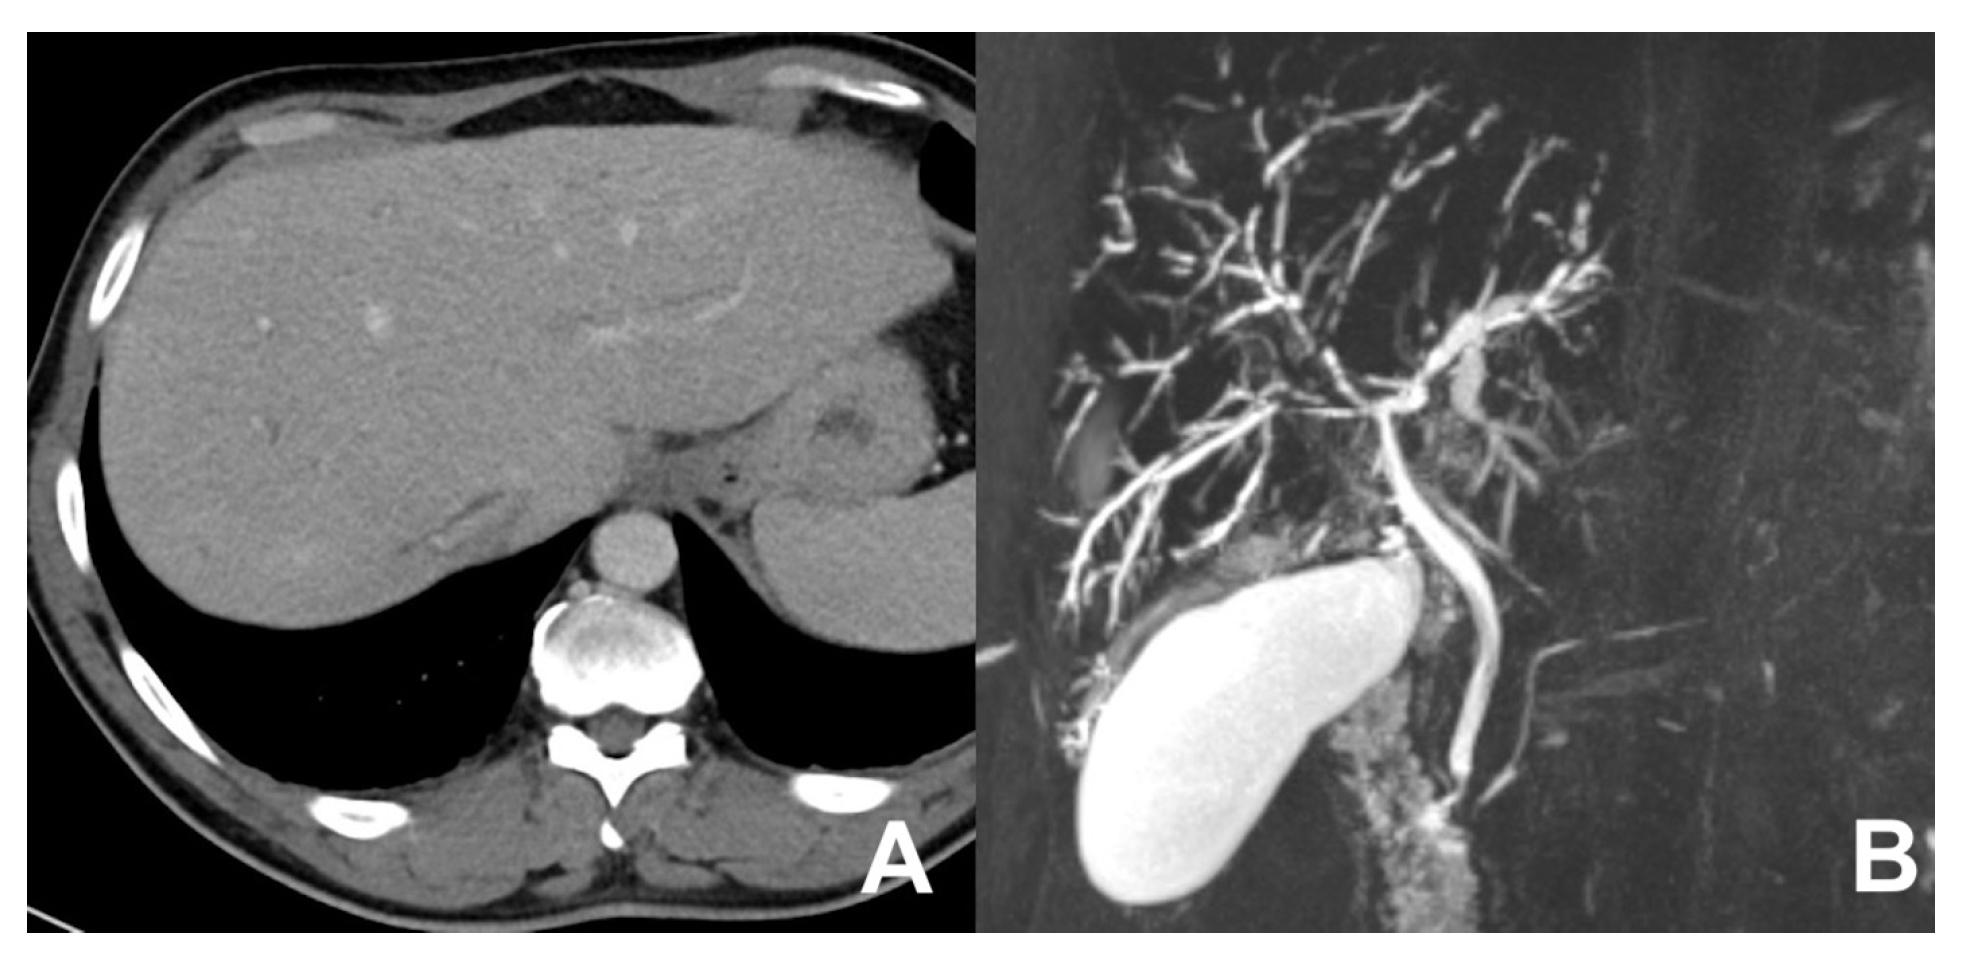

| Biliary leak after surgery or trauma | HASTE T2 | AXIAL | -- | -- | Anatomy and liquids analysis |

| INDICATIONS: MRI, thanks to the use of liver-specific MR contrast agents, can easily detect the site of bile leak. | HASTE T2 | CORONAL | -- | -- | Anatomy and liquids analysis |

| MRCP 3D | OBLIQUE CORONAL | -- | -- | Biliary anatomy and calculi | |

| GRE T1 IN/OUT | AXIAL | -- | -- | Steatosis | |

| GRE T1 3D DYNAMIC | AXIAL | Not necessary | YES high resolution | Useful for leak | |